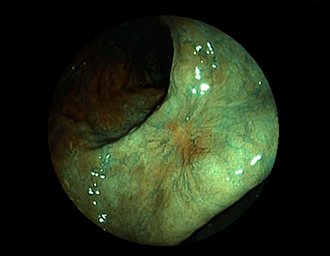

症例1:胃潰瘍(37才、男性)

①胃潰瘍(Stage A1)

健診:胃レントゲン検査で、胃角部ニッシェを指摘され当院受診。

胃角部小弯に、深くて大きな、大きさ約10mmの胃潰瘍(stage 1)があり、潰瘍底は一部白苔はみ出しを認める。エソメプラゾールマグネシウム水和物投薬で治療開始しました。